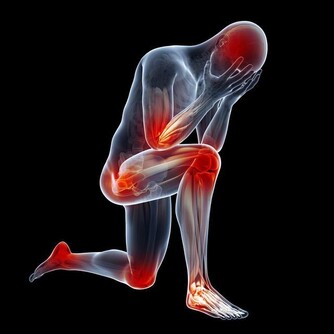

8.腰腿影響肝腎

我們都清楚腰不好就是腎虛的表現,因此來說腰靈活,那麼反之就是腎氣十分的充足。

而腿腳好的話則就是肝血旺盛的表示。想要腰腿靈活,那麼平時的運動非常的重要。